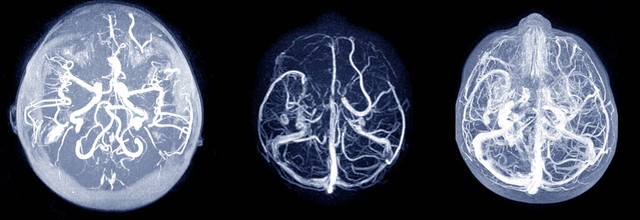

颅内大动脉的牵引、移位等刺激均可引起头痛。当刺激大脑前、中、后动脉时,若刺激离中线较远,则产生眼、额、颈部疼痛;若刺激在近中线处,则头痛为双侧性;其疼痛由三叉神经传导。后交通支动脉瘤可引起同侧额、眶周和眼深部痛,有时误诊为三叉神经痛和偏头痛。少数病例前交通动脉的动脉瘤可致额部痛,后颅凹动脉瘤可致枕部痛